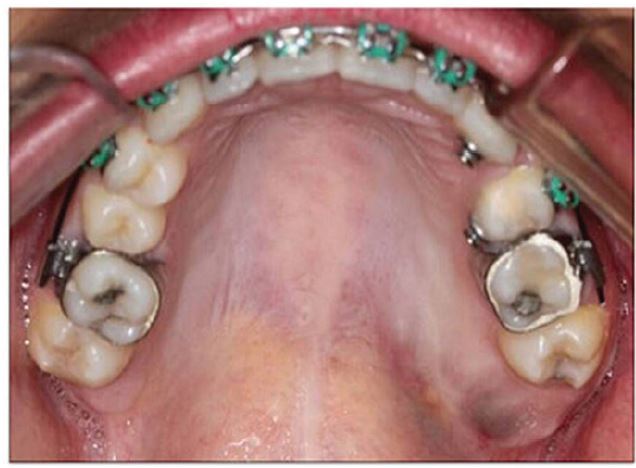

Clinical examination showed the absence of facial alterations and cervical lymphadenopathies. Intraoral examination revealed a swelling in the left posterior maxilla and pain on palpation (Figure 1). Computed tomography (CT) showed the presence of a hypodense lesion in the area of tooth 28 expanding to the maxillary sinus, but no cortical bone destruction (Figure 2).